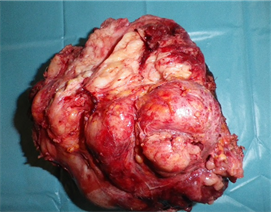

(a) (b)

Figure 4. Resected masses ((a) scrotal; (b) abdominal).